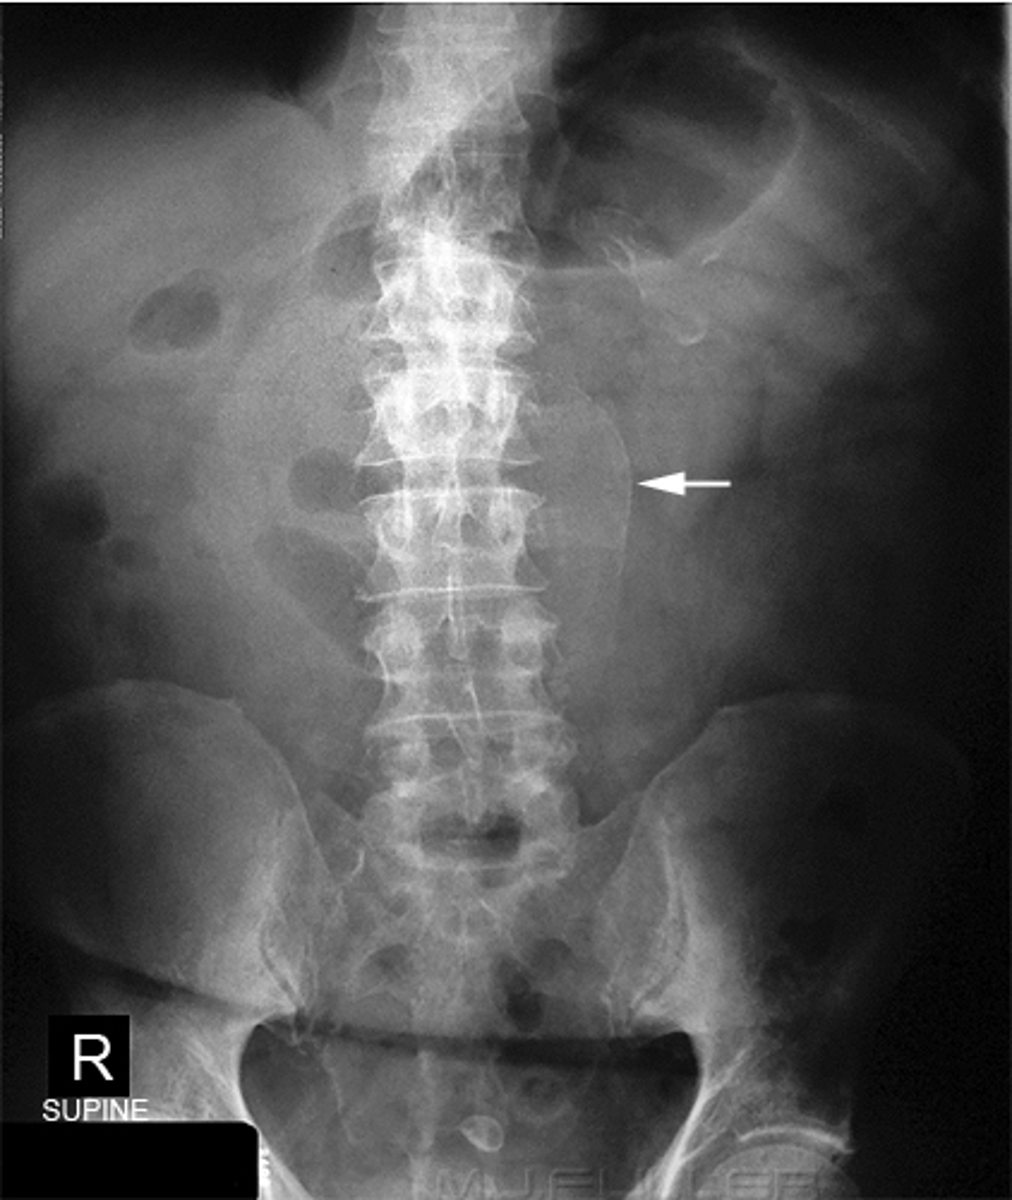

Generalized adynamic ileus, supine (A) and upright abdomen (B).

SOLID WHITE ARROWS: dilated loops of large bowel

DOTTED WHITE ARROWS: dilated loops of small bowel

SOLID BLACK ARROW: Rectum

Gas seen from small bowel to rectum. Patient had no bowel sound and had colon surgery the day before.